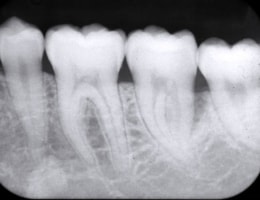

被曝量の少ない「デジタルレントゲン」を完備!

超高感度だから被曝量が軽減!子供さんにも優しいレントゲン!

デジタルレントゲンに使われているX線センサーは、デジタルならではの高感度!

照射時間が短縮され、より低線量でのレントゲン画像取得が可能となります。

当院のデジタルレントゲンは、

従来のフィルムを使用したレントゲン撮影に比べ、

人体に受ける放射線の量を、約1/4~1/10に抑える事が可能です。

現状を詳細に把握するため、小さいレントゲンを10枚撮って診断・治療をしております。

これにより歯石、歯周ポケット等も詳細に把握でき、緻密な治療を提供することが出来ます。